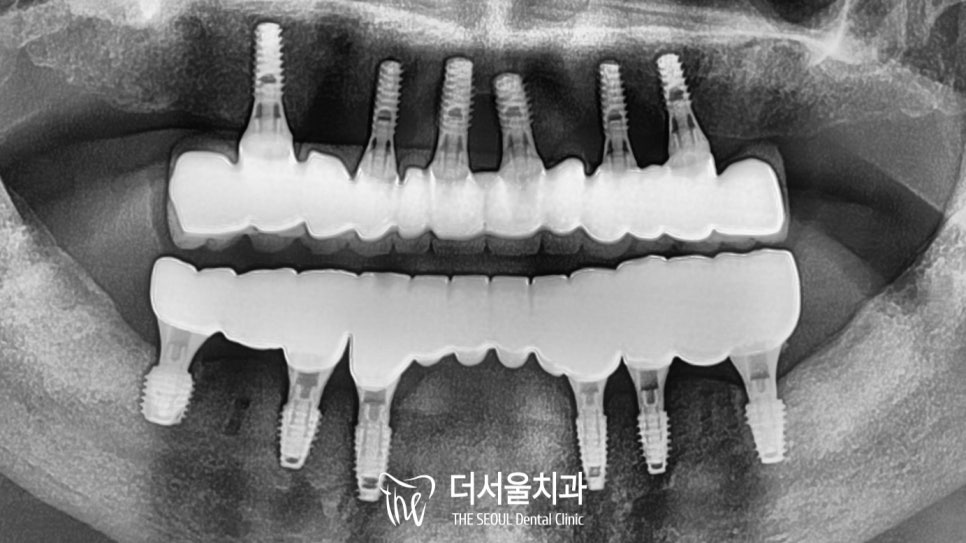

컴퓨터 분석을 토대로 결정된 식립 위치에

순차적으로 임플란트 를 심어드렸습니다.

이제 최종 보철 제작만을 앞두고 있는데요.

올바른 교합 이 형성되었는지 확인해야 됩니다.

더서울에서는 이런 문제들이 생기지 않도록

기존의 교합 과 주변 조직들의

위치를 분석하여 제작하는데요.

이때 새로운 높낮이에도 불편하지 않도록

충분한 적응 시간도 함께 부여하고 있죠~

치료 기간 2022.08.03 ~ 2022.11.15